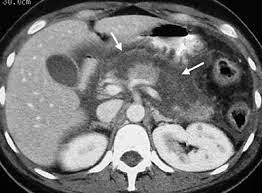

• Απεικονιστικές εξετάσεις όπως η απλή ακτινογραφία θώρακος και κοιλίας, το υπερηχογράφημα, η αξονική ή η μαγνητική τομογραφία κοιλίας αλλά και η ΕRCP (ενδοσκοπική ανάστροφη χολαγγειοπαγκρεατογραφία) ή η MRCP (μαγνητική χολαγγειοπαγκρεατογραφία), εάν κριθεί απαραίτητο.

Η αξονική τομογραφία δίνει μια καλή αξιολόγηση των παγκρεατικών αλλοιώσεων και την ύπαρξη περιπαγκρεατικής νέκρωσης και εξιδρωμάτων. Ο όγκος των εξιδρωμάτων και η έκταση της νέκρωσης του αδένα έχουν προγνωστική αξία.

Και οι δύο εξετάσεις επιτρέπουν, εάν είναι αναγκαίο, την διαδερμική κατευθυνόμενη παρακέντηση του παγκρέατος και των περιπαγκρεατικών συλλογών σε περίπτωση που υπάρχει υποψία για μόλυνση τους.

Κατά τη διάρκεια εξέλιξης, η ύπαρξη παγκρεατικής νέκρωσης εντός και εκτός του παγκρέατος και μόλυνση τους, η ανεπάρκεια άλλων οργάνων (πνεύμονες, ήπαρ, καρδιαγγειακά, κλπ) είναι σημάδια της βαρύτητας. Ο κίνδυνος των επιπλοκών αυτών αξιολογούνται από διάφορες μετρήσεις, από τις οποίες αυτές που χρησιμοποιούνται περισσότερο είναι: το σκορ Ranson, το Glasgow Coma Score και το SOFA. Τα επίπεδα της CRP και η αξονική τομογραφία έχουν επίσης μια ισχυρή προγνωστική αξία.